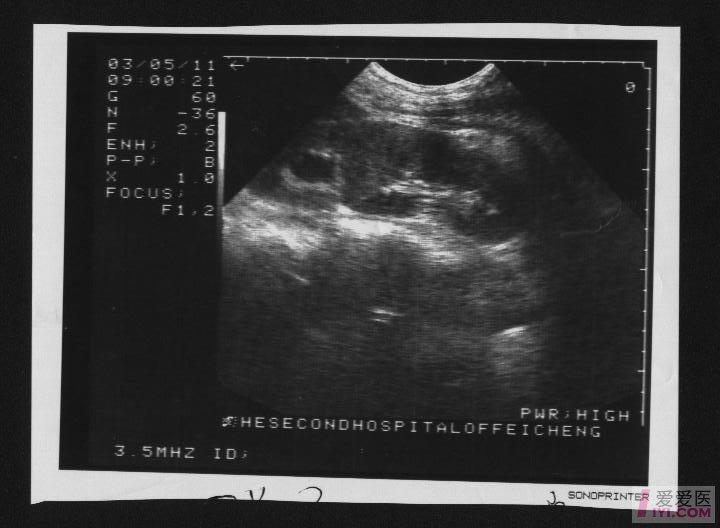

这是一个左肾的重复肾畸形合并左上肾积水.